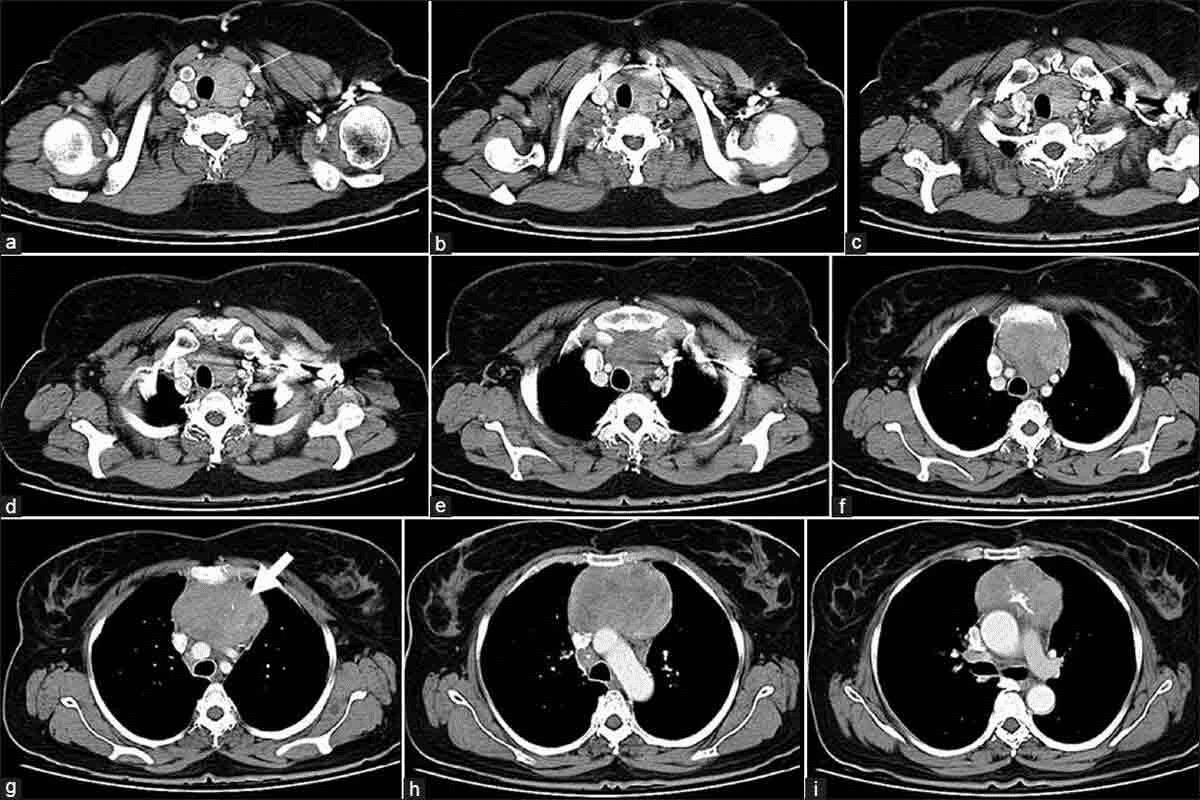

Advanced Imaging Techniques

For a closer look, advanced imaging techniques are used. These include:

- Magnetic Resonance Imaging (MRI): Gives detailed brain and blood vessel images.

- Cerebral Angiography: The top choice for finding brain aneurysms. It uses dye to see the aneurysm in the blood vessels.

- 3D Angiography: Shows the aneurysm in 3D, helping plan treatment.